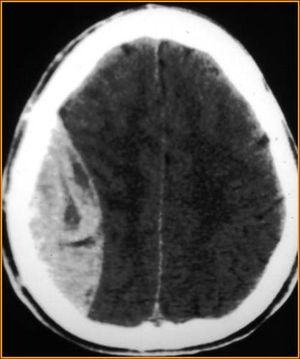

• Findings on CT are, classically, a lens (or lemon-shaped) shaped hyperdense lesion with sharp margins in the temporoparietal region

• Blood along the inside of the skull will not cross the sutures. This helps differentiate acute epidural hematoma from acute subdural hematoma.

Epidural hematoma with biconvex shape hemorrhage.